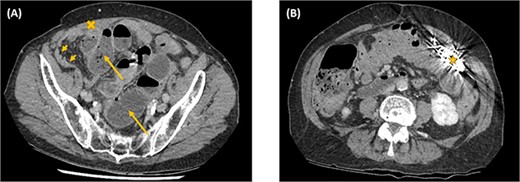

The abdominal computed tomography (CT) studies on all three recent admissions were consistent with SBO. The transition point was consistently seen in the right iliac fossa; with small bowel loops distended proximally with air-fluid levels and faecalised contents; and small bowel loops collapsed distally to the ileocaecal valve (Fig. 1A). There were no signs of bowel ischaemia or perforation. However, the preperitoneal ICD appeared to have migrated into the peritoneal cavity (Fig. 1B). On review of the serial abdominal CT studies over the past two years, the ICD was in a different intraperitoneal location each time (Fig. 2). The recurrent episodes of SBOs were thus believed to be related to the ICD, due to either intraperitoneal migration of the device or formation of adhesions from its placement, given the coinciding timeline.

Axial computed tomography images showing small bowel obstruction with a transition point in the anterior right iliac fossa (cross). There are distended small bowel loops proximally with air-fluid levels and faecalised contents (arrows); and collapsed small bowel loops distally (arrow heads). The ICD is located intraperitoneally (star).